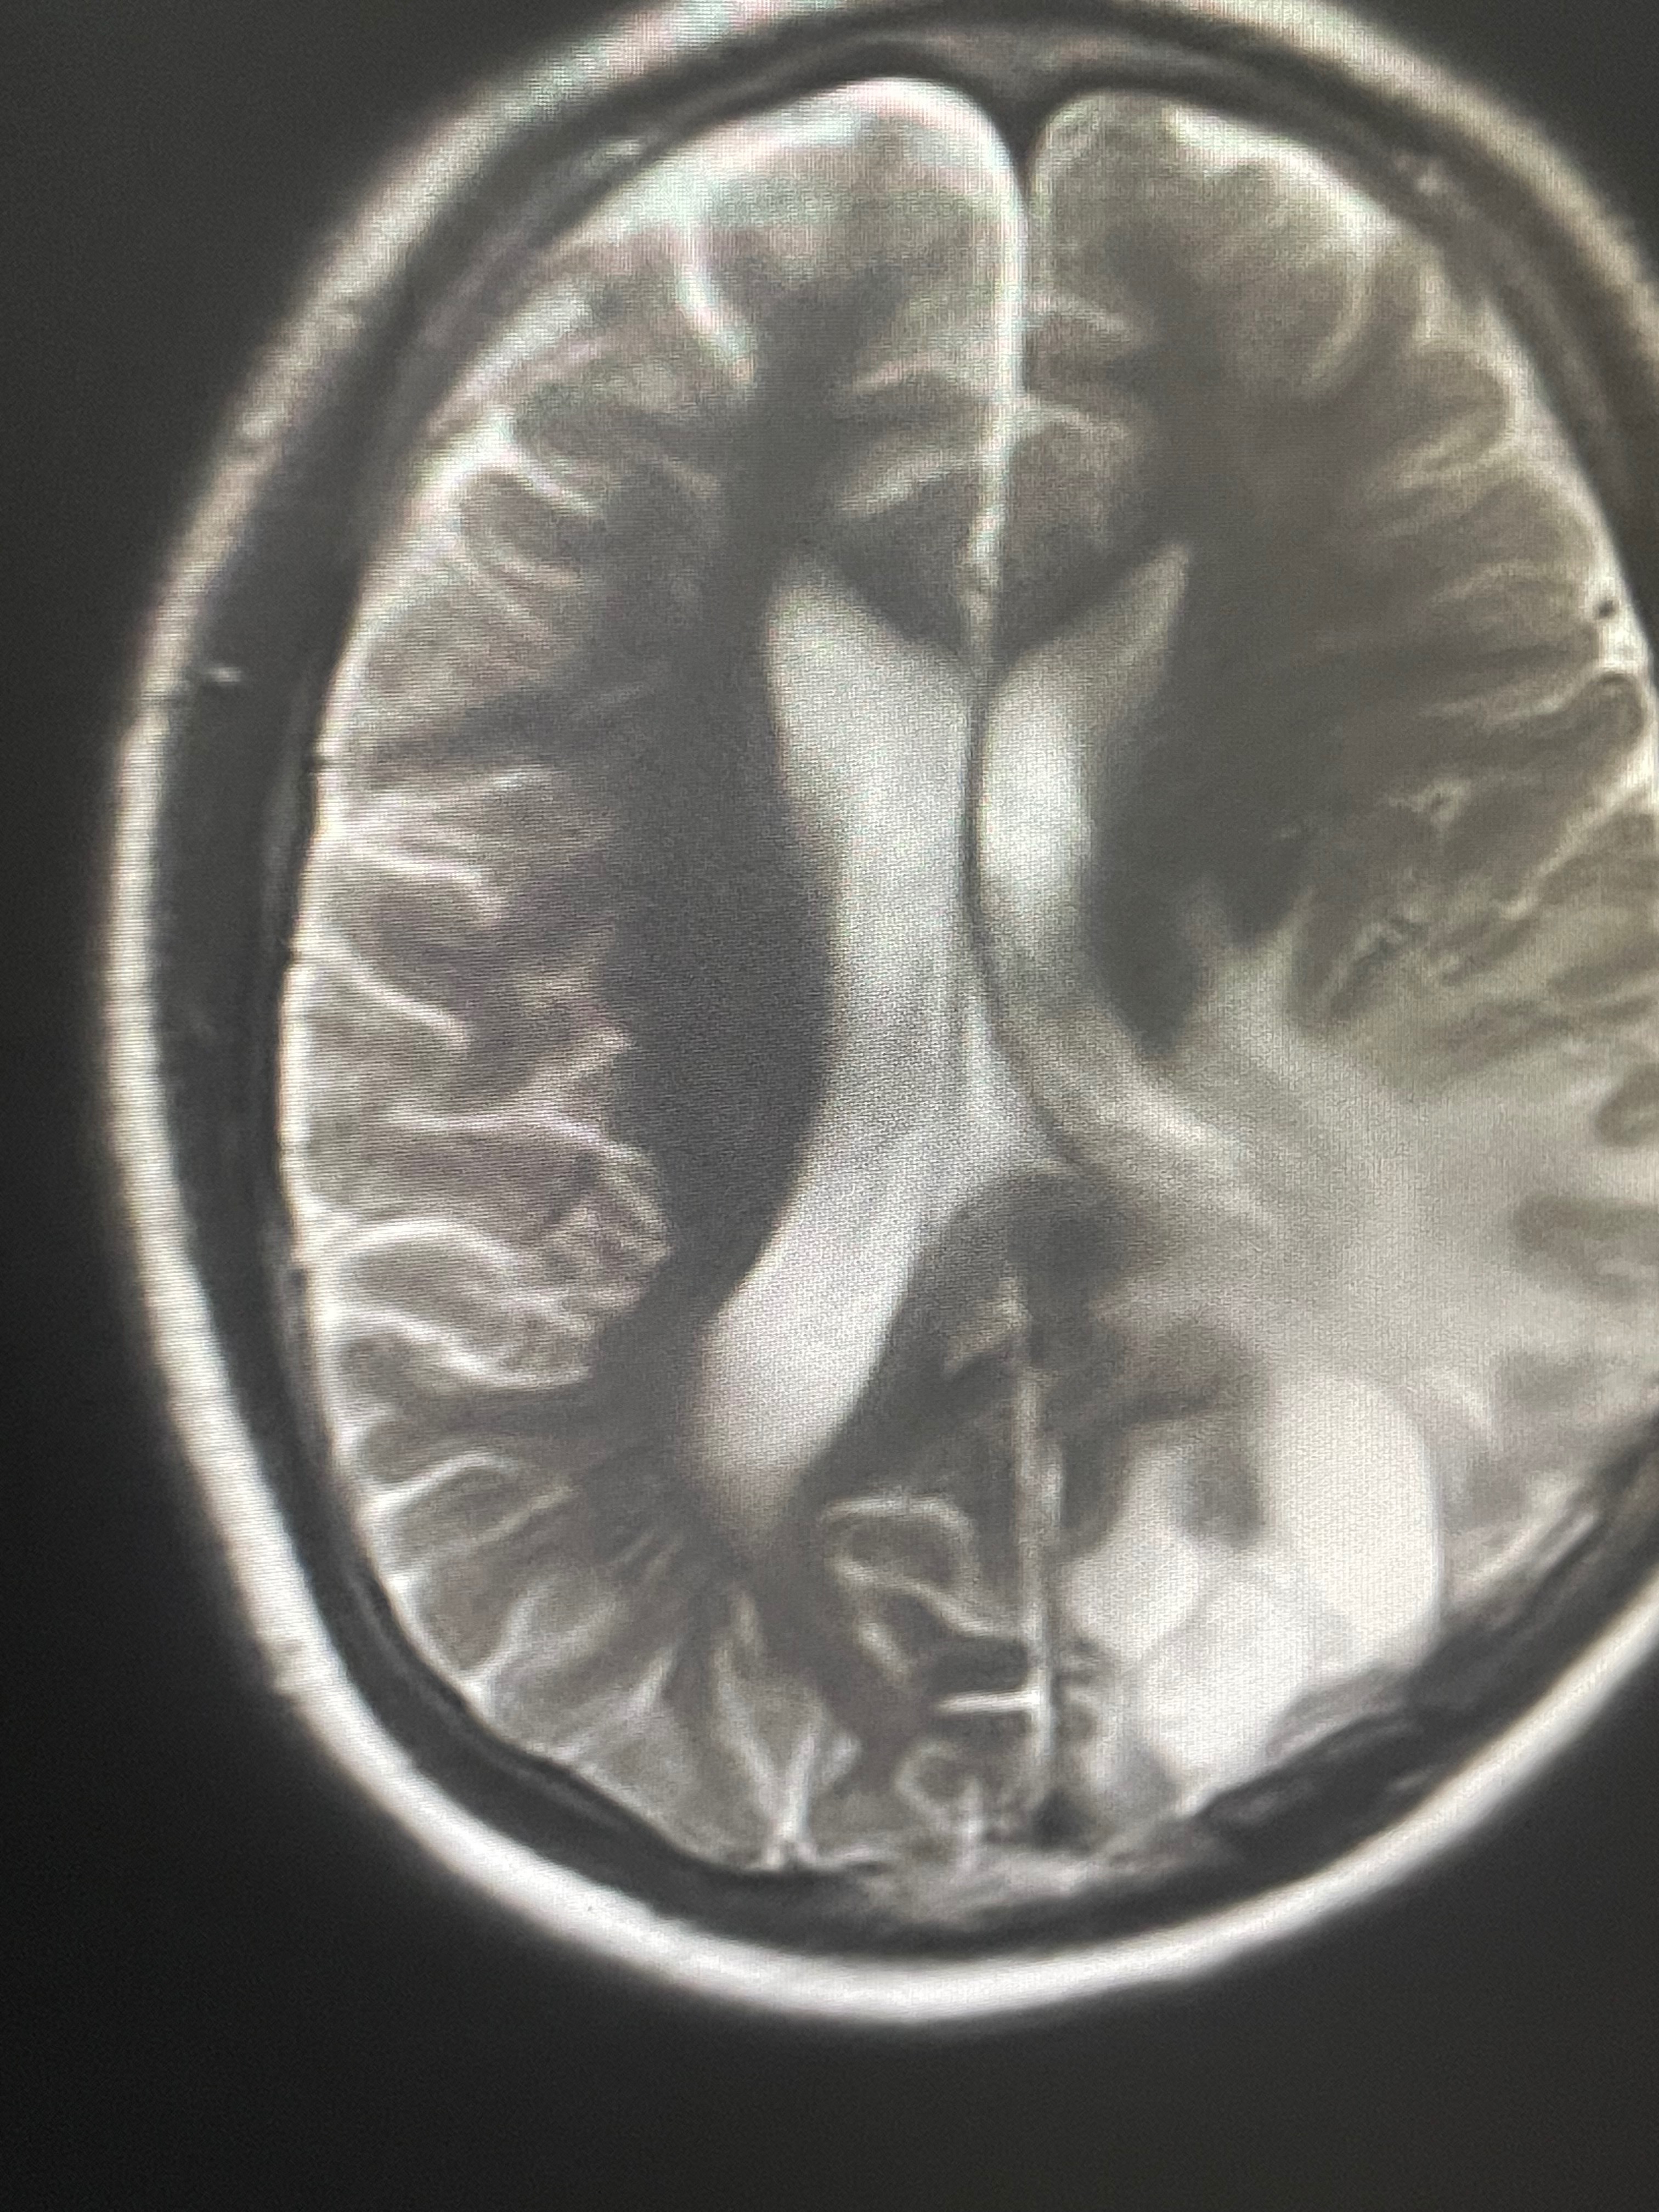

Orin, a 18 year-old young man from Brooklyn, NY is fighting glioblastoma, one of the most aggressive and deadly forms of brain cancer. In the fight for his life and due to this diagnosis, he has already undergone two brain surgeries and suffers multiple epileptic seizures. Despite everything he has endured, there is still hope.. but time is critical.